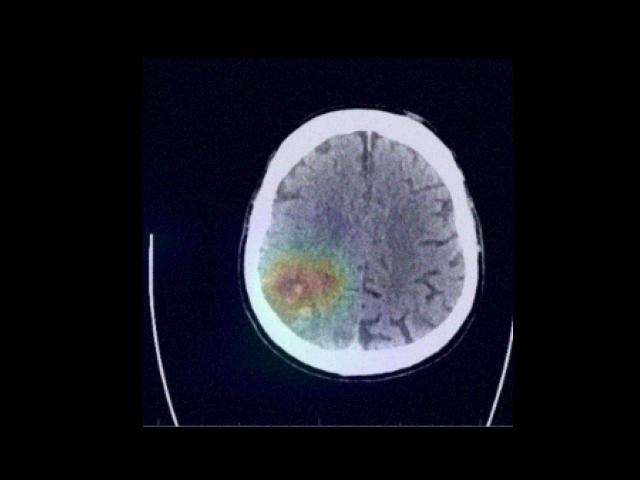

Sample Gallery